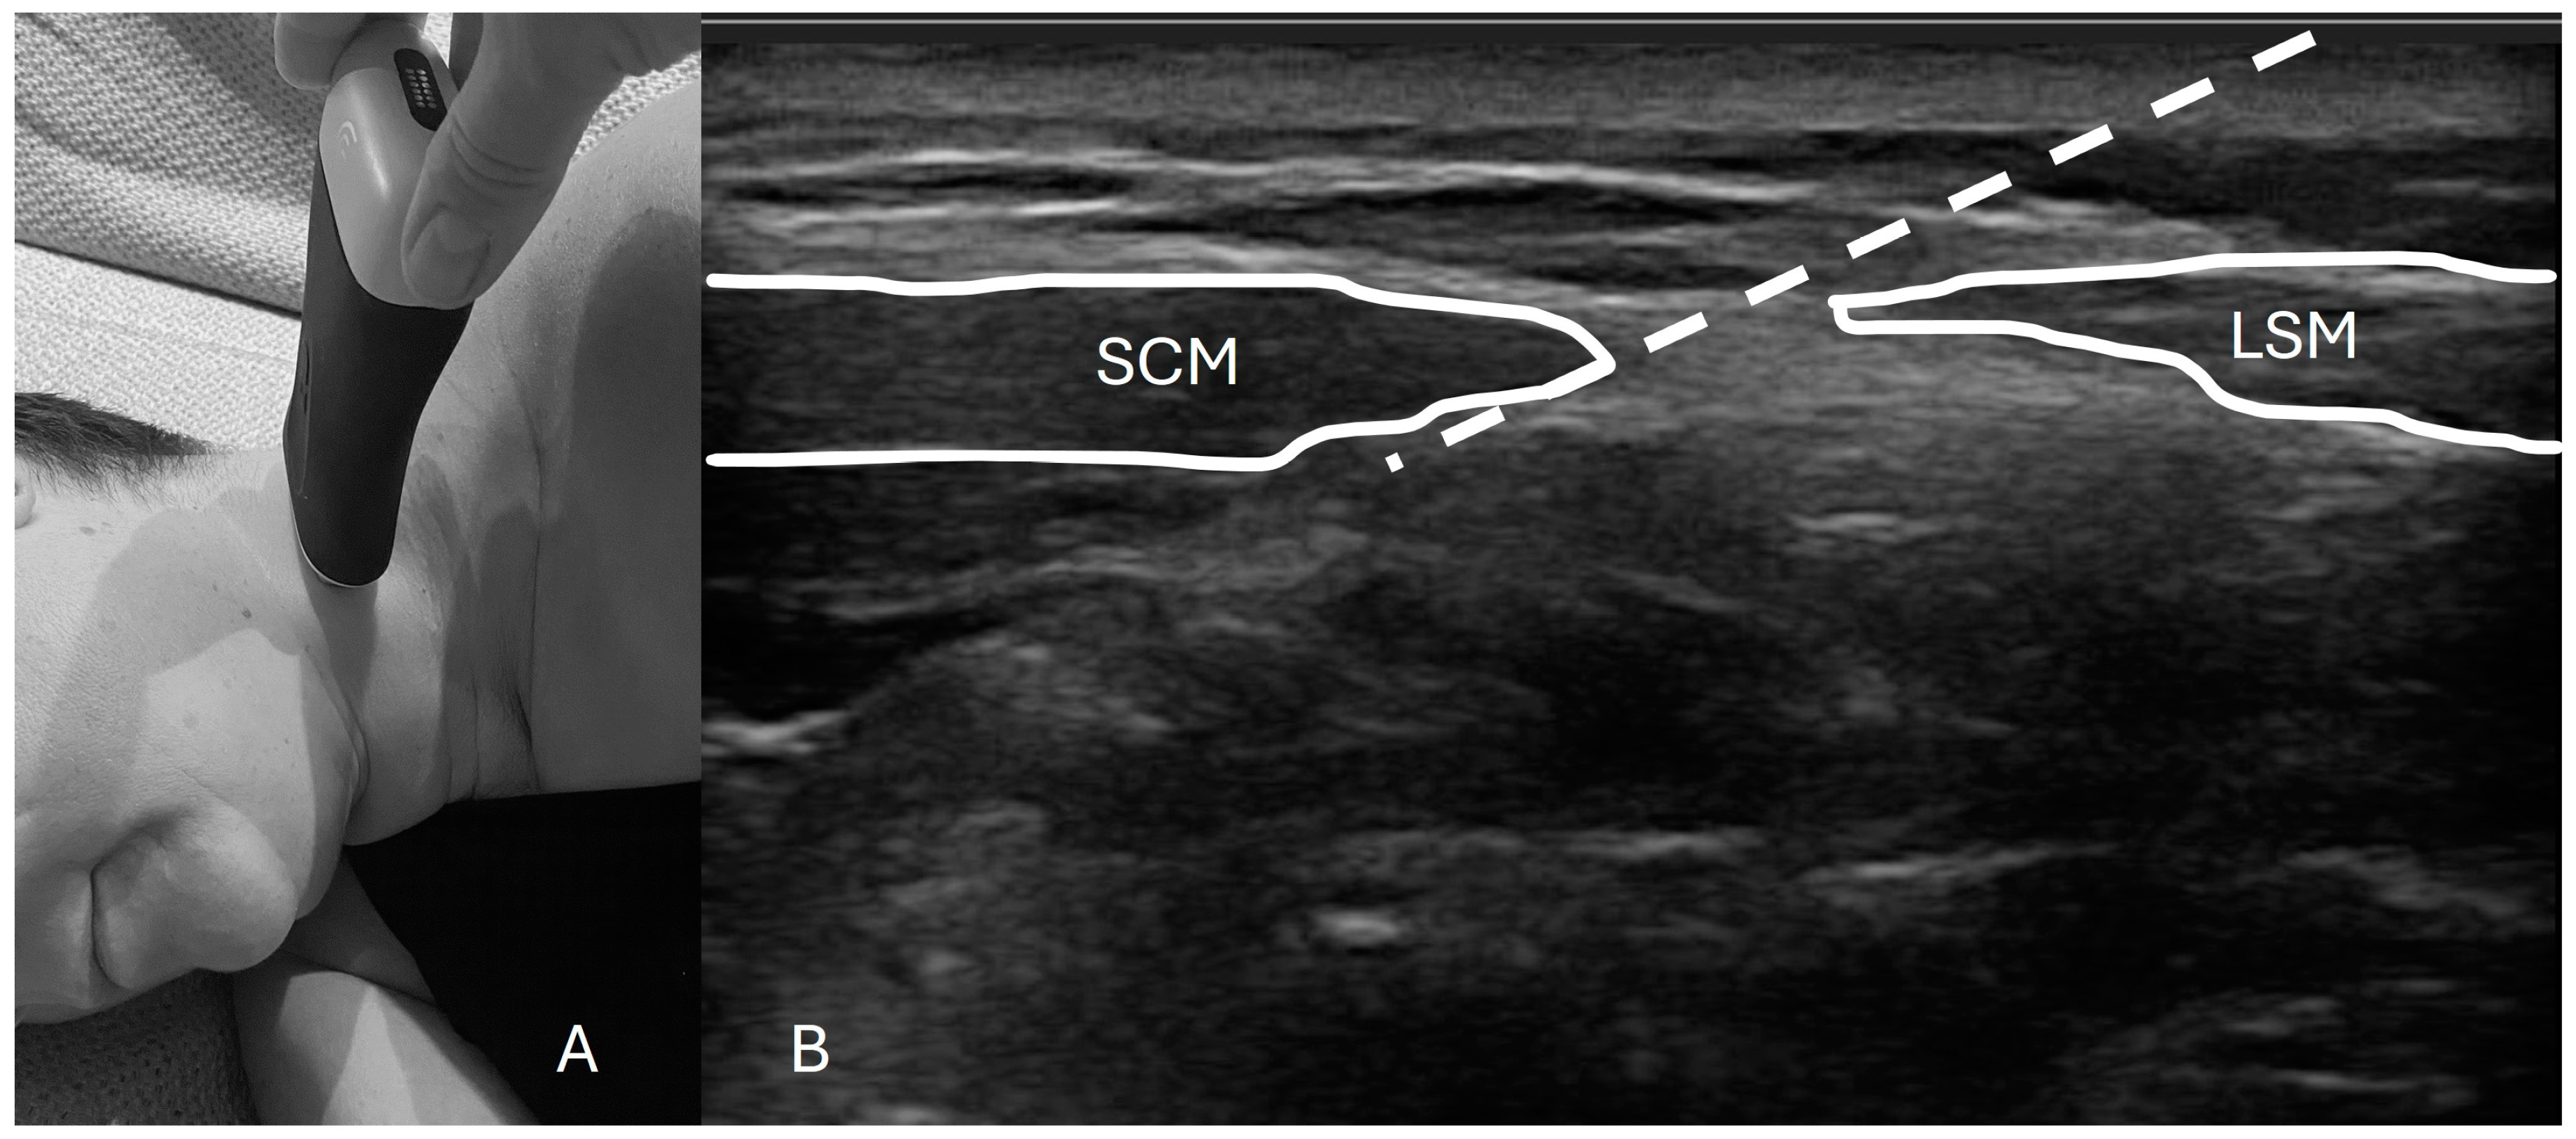

To perform this technique, one must first identify the posterior border of the sternocleidomastoid (SCM) muscle extending from the mastoid process (most cranial insertion of the SCM) all the way down to the lateral projection of the C6 vertebrae. The US probe should provide an axial cut of the neck at the midpoint of the line of the SCM to a height close to the cricoid cartilage. With an “in-plane” approach, the needle is inserted and lands no more than 1 to 2 cm antero-medially under the SCM (Figure 1). After negative aspiration, a volume of local anesthetics is deployed underneath the SCM anterior to the levator scapulae muscle while being careful not to pierce through the prevertebral fascia[4,6]. Figure 1 shows an example of a typical setup for this procedure.

Figure 1. Probe placement and ultrasound image with landmarks. A: The patient is positioned in the lateral decubitus position with the ultrasound probe placed approximately at the middle third of the sternocleidomastoid muscle (SCM). B: An axial ultrasound scan of the cervical area shows the SCM and levator scapulae muscle (LSM). The white striped line indicates the needle trajectory, with the final dot marking the anatomical target for the injection.